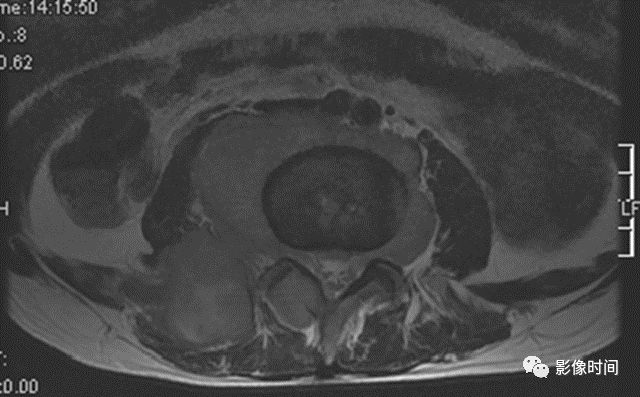

九、瘤周水肿

肿瘤周边的骨髓水肿表现为 T1WT 低信号和 T2WI、STIR 高信号边界模糊的片状影,软组织肿块邻近的正常软组织成分,尤其是肌肉内亦可出现水肿,表现为肿块周围沿肌束方向分布的边界模糊的片状或羽毛状影,有时可连成片。瘤周水肿常见于恶性肿瘤(图 58),但也可见于某些良性肿瘤如软骨母细胞瘤(图 59)、骨样骨瘤和骨嗜酸性肉芽肿(图 60)等。

图 58   瘤周水肿:骨肉瘤